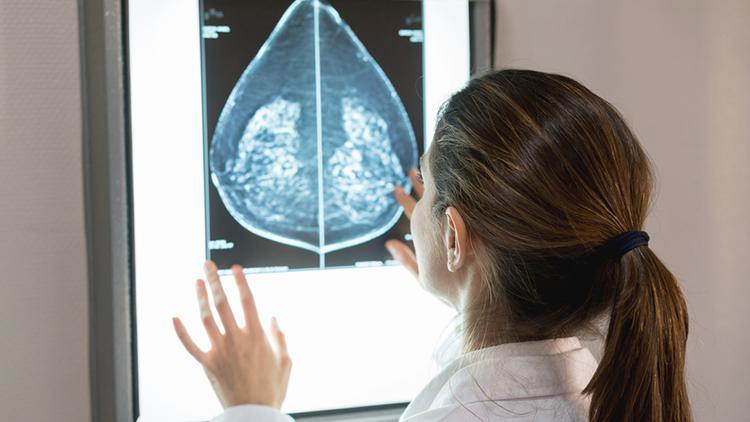

İsveç’te yapılan bir araştırma, yapay zekanın meme kanseri için çekilen röntgenleri inceleyerek kanseri tespit edebileceğini ortaya koydu.

Lund Üniversitesi’nden bilim insanları, yapay zekanın tespit başarı oranının iki radyologla birlikte yapılan normal teşhis süreciyle aynı olduğunu açıkladı.

İngiltere’de daha önce yapılan yapay zeka denemeleri, geçmişte teşhis edilmiş meme kanseri röntgenleri üzerinden çalışırken; bu seferki araştırma, iki radyoloğun teşhis süreciyle eş zamanlı yürütüldü.

Lancet Oncology adlı hakemli dergide yayımlanan araştırmada İsveç’te ortalama 54 yaşındaki 80 binden fazla kadının mamografisi incelendi.

Görüntülerin yarısı normal prosedür olan iki radyolog tarafından incelenirken, diğer yarısı da yapay zeka tarafından incelendikten sonra bir veya iki radyoloğa sunuldu.

Standart yöntemde radyologlar 203 meme kanseri tespit ederken, yapay zeka 244 kadında meme kanseri olduğunu saptadı.

Yapay zekanın yanlış pozitif, yani meme kanseri olmayan birine kanser teşhisi koyma oranı da normal prosedürle aynı çıktı: Yüzde 1,5.